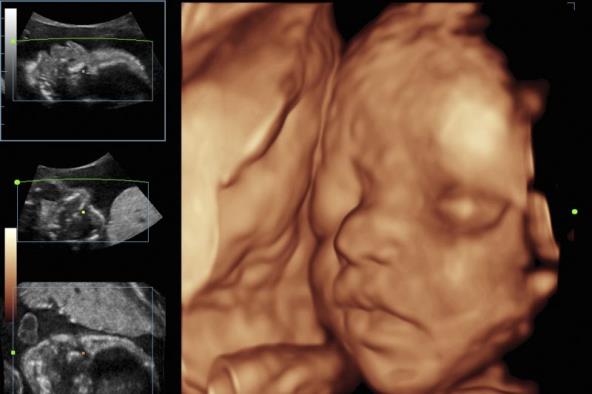

3D - TRODIMENZIONALNI PRIKAZ: Pomoću ovog ultrazvuka prikazuje se trodimenzionalna slika ploda, tačnije samo njegov fizički izgled. Tu se utvrđuju fizičke mane, kao na primer da li detetu nedostaje neki organ, na primer usna ili ruka, kao i da li su se nos i disajni putevi razvili.

4D - ČETVORODIMENZIONALNI PRIKAZ: Prikazuje potpunu sliku ploda u stvarnom vremenu. Ovo je najkompletniji snimak iz razloga što prati rad mozga, fetalnu dinamiku i ponašanje, izgled ploda i još mnogo toga. Najvažniji element je da ovaj snimak može da uvudi da li dete ima anomalije.